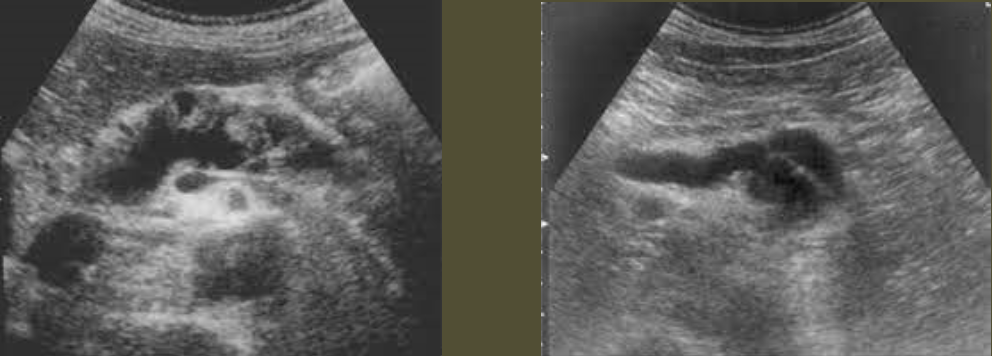

Hydatid Disease/Echinococcal Cyst → infectious, parasitic disease (tapeworm) in sheep-herding areas

2D US: water lily sign (infolding from collapsed wall), cyst w/ daughter cells, outer wall calcifications,

color doppler: avascular

DDX: amebic abscess, pyogenic abscess